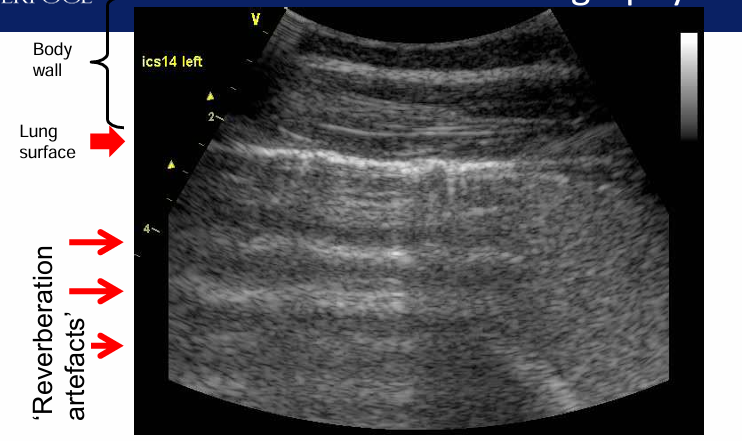

Ultrasound